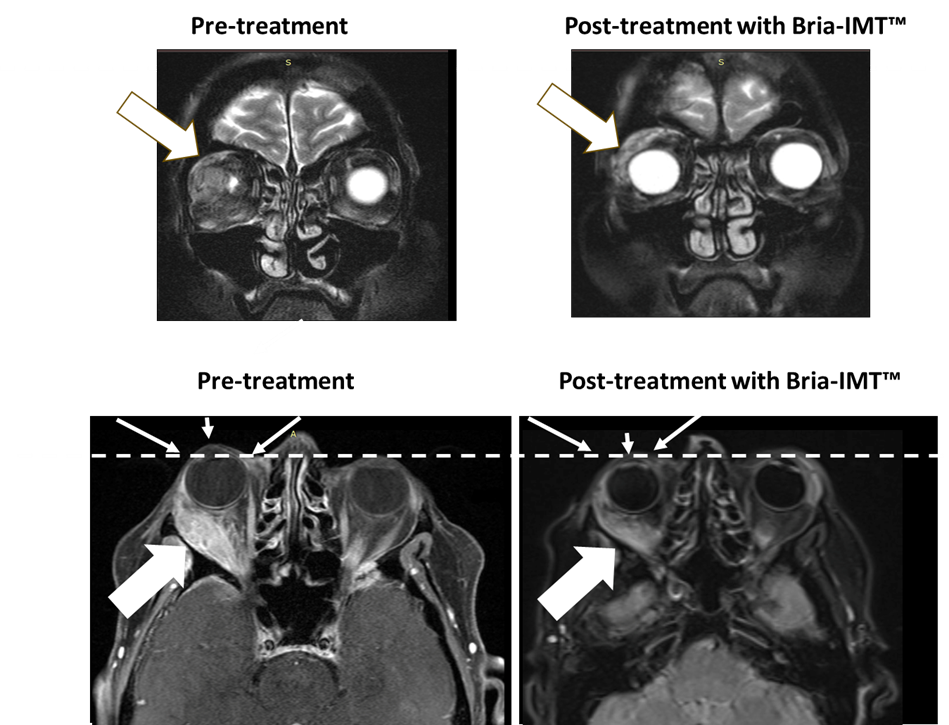

BriaCell Images Confirm Robust Anti-Tumor Activity in Patient with “Eye-Bulging” Metastatic Breast Cancer

Figure 1

- Significant reduction of metastatic breast cancer tumor behind-the-eye after only 3 cycles

- Powerful anti-tumor response associated with reduction in proptosis (eye-bulging) and reduced ocular pain

PHILADELPHIA and VANCOUVER, British Columbia, Jan. 04, 2024 (GLOBE NEWSWIRE) — BriaCell Therapeutics Corp. (Nasdaq: BCTX, BCTXW) (TSX: BCT) (“BriaCell” or the “Company”), a clinical-stage biotechnology company that develops novel immunotherapies to transform cancer care, is pleased to release transformational images of the recently reported remarkable responder in the Phase 2 study of BriaCell’s Bria-IMT™ combination regimen. The patient had metastatic breast cancer behind her eye, causing proptosis (eye-bulging) and significant pain that were both markedly reduced with BriaCell’s treatment.

“We are extremely excited to report significant tumor reduction in this very difficult to treat patient who had failed 7 prior regimens including treatment with Enhertu®, an antibody-drug conjugate, highlighting the robust anti-tumor activity of the Bria-IMT™ regimen in difficult to reach tumors such as those in the eye orbit. We observed significant tumor reduction along with significant eye pain reduction after only 3 cycles of treatment with the Bria-IMT™ combination regimen. The Bria-IMT™ regimen has been very well tolerated and the patient remains on treatment,” stated Dr. William V. Williams, BriaCell’s President and CEO. “We look forward to sharing additional data in the coming months.”

The following figure shows magnetic resonance imaging (MRI) of the orbital tumor. The top left MRI image shows the tumor in the right orbit behind the eye with the eye not being visible pre-treatment. After treatment with the Bria-IMT™ regimen, the eye becomes visible (top right image) as it has regained its normal position. In the lower images, the dashed line represents normal margin of eye position with resolution of proptosis post treatment (small arrows) with the Bria-IMT™ regimen. Reduction in tumor is represented by large arrows.

BriaCell had previously reported a similar case of a remarkable response with resolution of an eye-bulging orbital tumor. That particular patient had received (and failed) 12 regimens with 16 agents (incl. 13 chemotherapies) prior to BriaCell’s combination therapy, again adding to the remarkable nature of her response. These two patient responses are included in BriaCell’s recently reported 71% intracranial objective response rate (iORR) in breast cancer patients with Central Nervous System (CNS) metastases treated with Bria-IMT™.

“Today’s reported MRI imaging confirms the clinical response seen and supports the further development of our Bria-IMT™ regimen. Women with metastatic breast cancer continue to have poor survival despite recently approved therapies and further development of novel treatments remains an area of high unmet medical need,” stated Dr. Giuseppe Del Priore, BriaCell’s Chief Medical Officer.